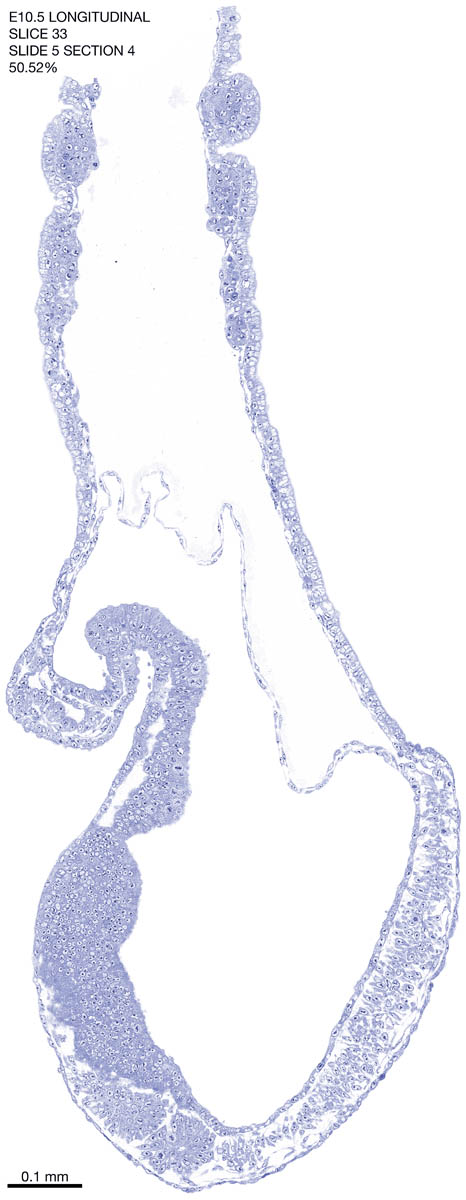

E10.5 Longitudianal Archive This page contains jpg files of ALL SLICES (each 3µm thick) that were scanned of the E10.5 longitudinally cut specimen. Download: Large | High Res Download: Large | High Res Download: Large | High Res Download: Large | High Res Download: Large | High Res Download: Large | High Res Download: Large | High Res Download: Large | High Res Download: Large | High Res Download: Large | High Res Download: Large | High Res Download: Large | High Res Download: Large | High Res Download: Large | High Res Download: Large | High Res Download: Large | High Res Download: Large | High Res Download: Large | High Res Download: Large | High Res Download: Large | High Res Download: Large | High Res Download: Large | High Res Download: Large | High Res Download: Large | High Res Download: Large | High Res Download: Large | High Res Download: Large | High Res Download: Large | High Res Download: Large | High Res Download: Large | High Res Download: Large | High Res Download: Large | High Res Download: Large | High Res Download: Large | High Res Download: Large | High Res Download: Large | High Res Download: Large | High Res Download: Large | High Res Download: Large | High Res Download: Large | High Res Download: Large | High Res Download: Large | High Res Download: Large | High Res Download: Large | High Res Download: Large | High Res Download: Large | High Res Download: Large | High Res Download: Large | High Res Download: Large | High Res Download: Large | High Res Download: Large | High Res Download: Large | High Res Download: Large | High Res Download: Large | High Res Download: Large | High Res Download: Large | High Res Download: Large | High Res Download: Large | High Res